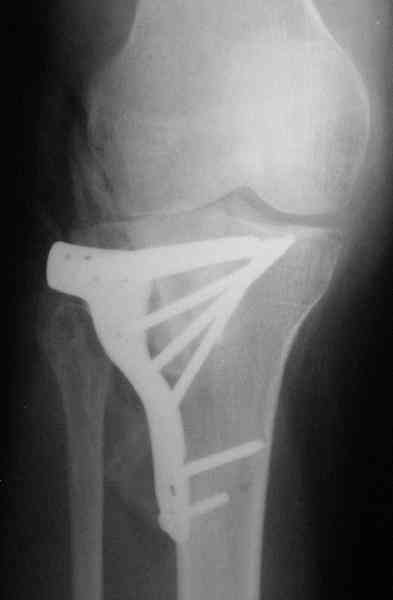

Уважаемый Абдурашид. Если нет противопоказаний , то из оперативных способов, я бы рекомендовал следующие: Полное замещение наружного мыщелка аллотрансплантатом либо открытая репозиция с элевацией и замещение дефекта ауто или аллокостью. В Ваших условиях , я бы рекомендовал второй способ. Во-время элевации необходимо разъединить фрагменты со стороны сустава ( надсечь скальпелем по линиям перелома, а затем тонким остеотомом их разъединить. При помощи долота произвести неполную остеотомию ( захватите не менее 1,5 - 2 см губчатой кости и поднять фрагменты, визуально отрепонировать и фиксировать 2-3 спицами. Дефект заместить костным ауто или аллатрансплантатом. Окончательная стабилизация пластиной ( лучше с угловой стабильностью, либо АВФ - позволит спокойно устранить угловую деформацию.